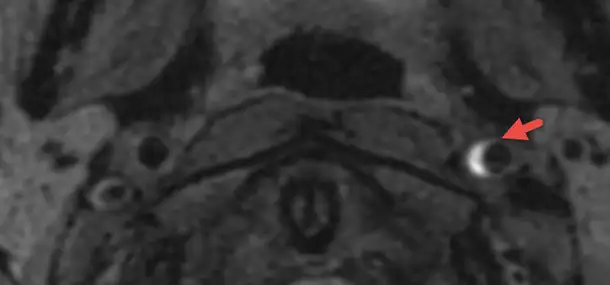

The MRI on the left side shows an area of bleeding (red arrow) in the wall of one of the large arteries that deliver blood to the brain. This injury of the wall of the artery lead to a stroke. The image on the right side shows the areas of the brain affected by the stroke (blue arrows).